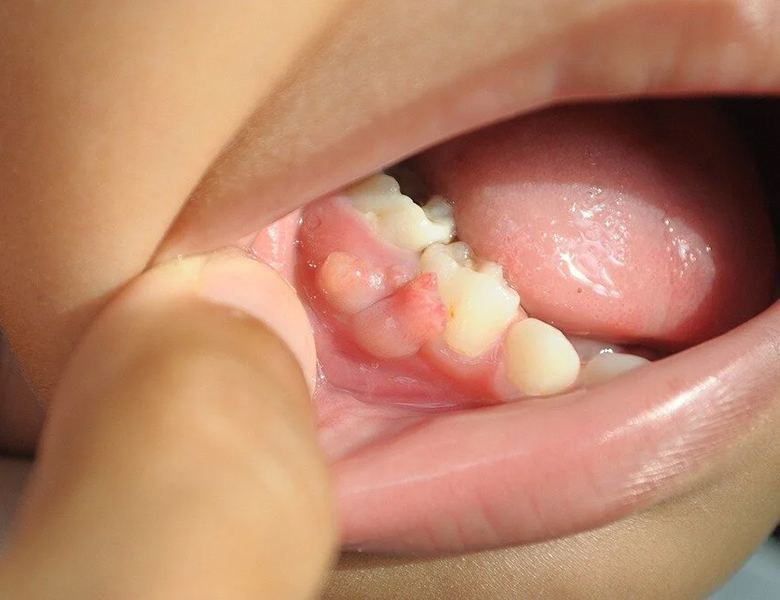

合わない入れ歯や被せ物による「床ずれ」(褥瘡性潰瘍)

入れ歯の縁(ふち)が当たっている場所や、尖った被せ物が当たる舌の横などにできるデキモノや潰瘍です。

持続的な物理的刺激によるものです。

触れると痛みがあり、原因となっている装置を外すと数日で改善します。

当院の対応

刺激の原因となっている被せ物を滑らかに研磨したり、入れ歯の調整を行ったりします。

調整後、数日で治癒するかを慎重に経過観察します。